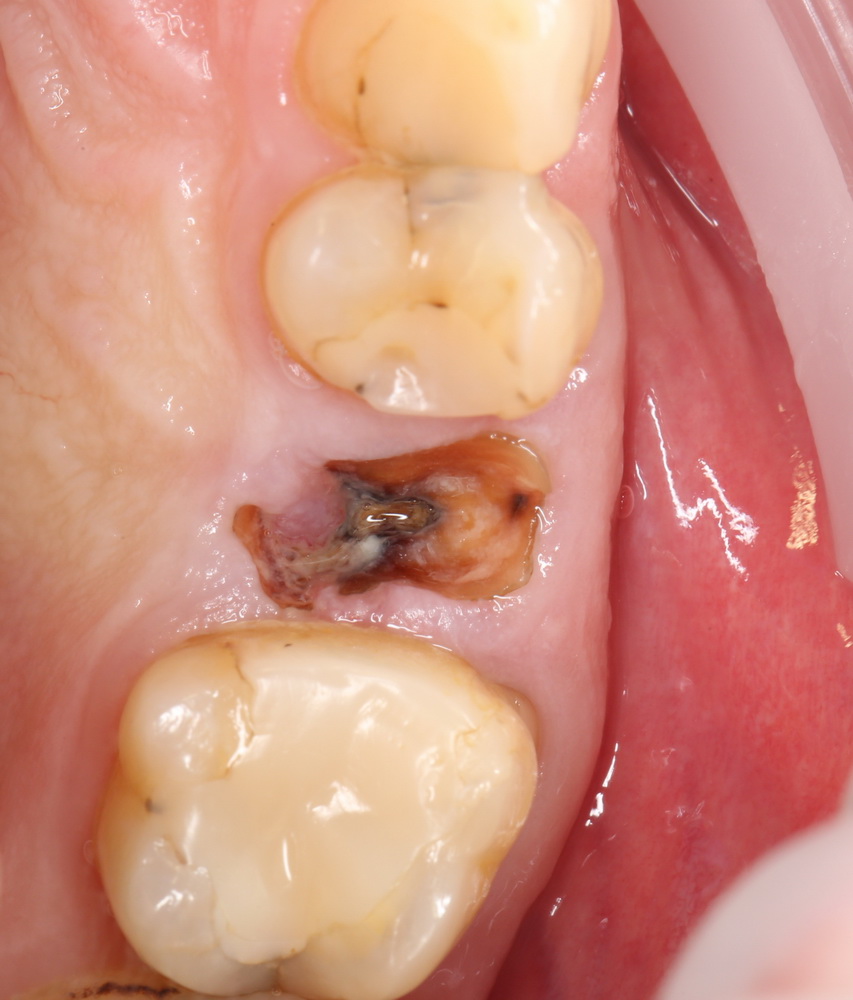

Мы встретились как старые друзья. Честно признаюсь, я очень переживал. Я ожидал увидеть какую-нибудь жуть, утраченную кость, периимплантит, разрушенный вхлам протез и всё такое. Но… всё оказалось не так плохо:

Но фиг с ними, с протезами. Это временные композитные коронки, их не так уж сложно заменить. Меня волнует другой вопрос:

— что там с имплантатами и костной тканью?

Для этого мы сделали КЛКТ:

И КЛКТ показала нам, что с имплантатами и окружающей костью всё зашибись. Через 12 лет после операции, отсутствия наблюдения, пофигизма в замене временных коронок! Нужны ли тебе еще какие-нибудь доводы в пользу долгосрочной эффективности метода?